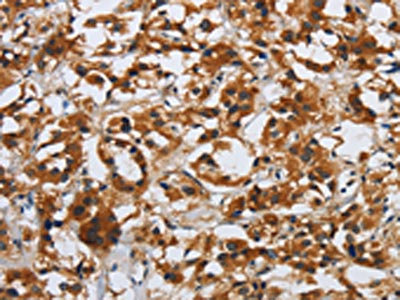

The image on the left is immunohistochemistry of paraffin-embedded Human thyroid cancer tissue using CSB-PA921679(DSP Antibody) at dilution 1/40, on the right is treated with synthetic peptide. (Original magnification: ×200)

The image on the left is immunohistochemistry of paraffin-embedded Human esophagus cancer tissue using CSB-PA921679(DSP Antibody) at dilution 1/40, on the right is treated with synthetic peptide. (Original magnification: ×200)